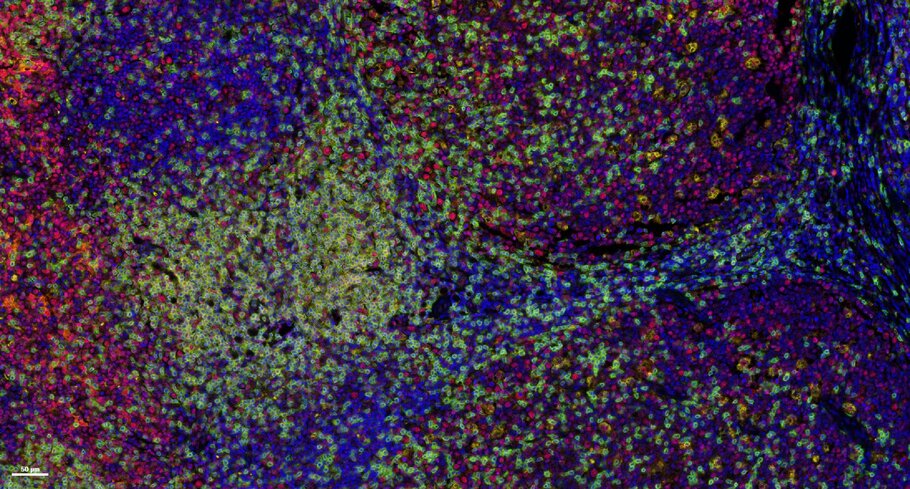

Tumor Microenvironment

Many immunotherapeutic interventions must penetrate the tumor microenvironment to exert their effect. Learn about the complexities of the tumor microenvironment and its component cancer cells, immune cells, vasculature, and stromal cells.